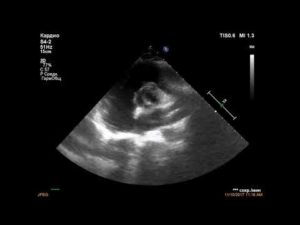

| Эхокардиография |

|

Основной диагностический метод – УЗИ. Это единственный способ подтвердить присутствие двустворчатого аортального клапана. Остальные исследования требуются для уточнения степени поражения и подбора лечебных мероприятий.

- Нарушение подтверждается на ЭхоКГ. Ультразвуковой метод выявляет увеличение камер сердца и неполное закрытие митрального отверстия.